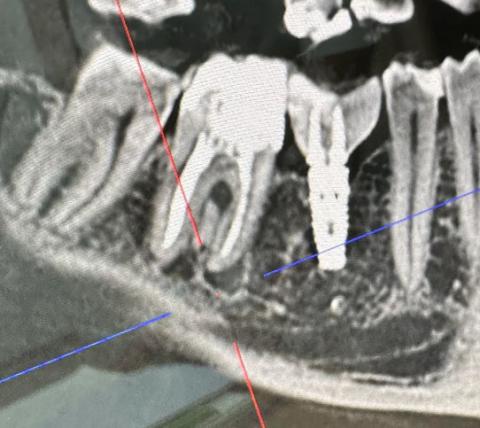

This CBCT image shows a posterior mandibular area with a natural molar next to an existing dental implant. The natural tooth presents a clear apical radiolucency, indicating infection at the root apex. Bone density changes are visible between the infected tooth and the implant site.

-

Natural molar with deep restoration

Visible apical lesion at root tip

Adjacent implant appears integrated

Localized bone loss near apical area

Cortical bone still intact

Periapical radiolucency suggests chronic apical periodontitis

Bone trabeculation is reduced near infection site

Infection is in close proximity to implant threads

No immediate implant mobility, but risk is present